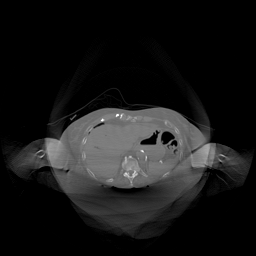

The results for simulated noisy data are shown in Fig. 2. The first and third rows display two representative slices from the test set, and the second and fourth rows present the corresponding error maps. The traditional WCE method suppresses cupping artifacts and recovers some missing anatomical structures but still shows noticeable deviations from the ground truth. Predictions from the four diffusion-based models demonstrate a markedly improved ability to restore anatomical structures. Among them, cDDPM fails to fully reconstruct the patient bed and retains residual noise in its outputs. This noise is attributable to an incomplete reverse denoising process rather than residual Poisson noise, as evidenced in our noise-free experiments (Fig. 5 in the Appendix). PatchDiffusion, diffusionGAN, and I2SB achieve similar visual quality, with I2SB producing the cleanest and most consistent reconstructions.

Quantitative results in Tab. V further confirm I2SB’s superiority over conventional deep learning methods such as FBPConvNet and Pix2pixGAN across RMSE, PSNR, and SSIM. Compared to other diffusion models—including cDDPM, PatchDiffusion, and cLDM—I2SB delivers higher image quality, while diffusionGAN achieves comparable quantitative performance. However, I2SB demonstrates a significant advantage in inference efficiency, as summarized in Tab. IV.